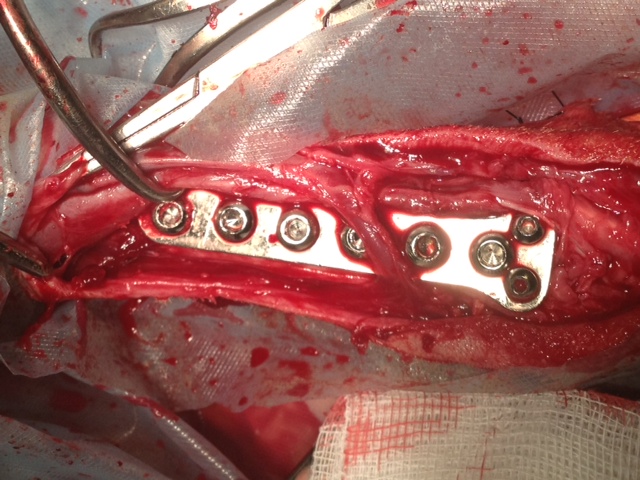

Heute hatte Felipa ihren ersten OP-Termin.

Wir waren alle sehr aufgeregt. Und selbst der erfahrene Arzt meinte, es sei eine ungewöhnliche Aktion, denn normalerweise weist nur ein Pfötchen so starke Anomalien auf. Er hatte es noch nicht, dass beide operiert werden müssen.

In sechs Wochen erfolgt dann die zweite OP.